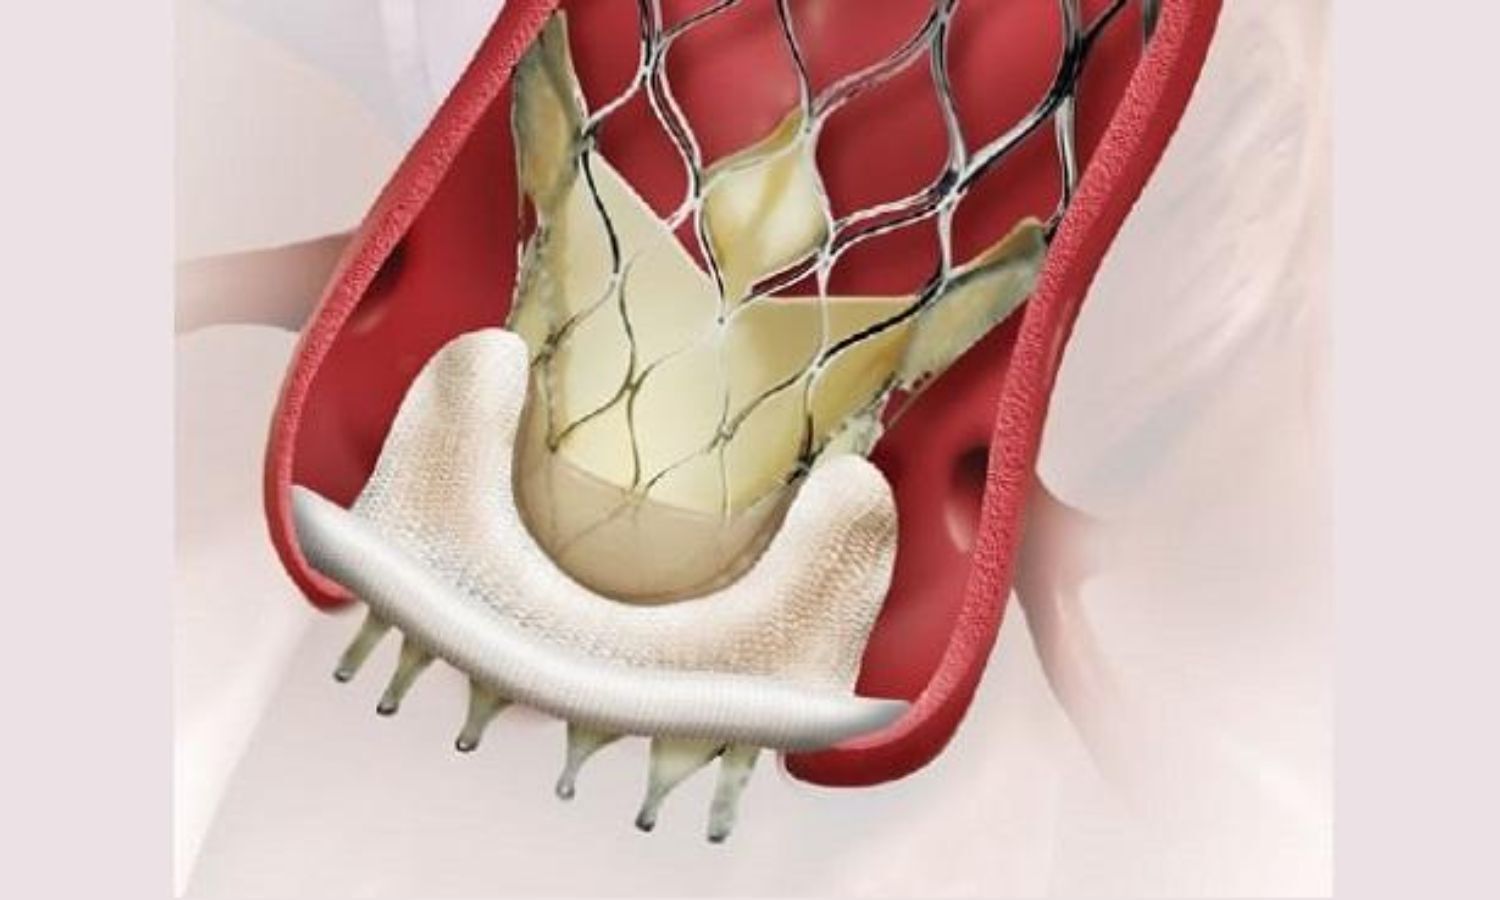

On-X® Life's Chord-X™ Mitral Valve Chordal Repair System Launched At

www.medlatest.com

www.medlatest.com

chord mitral valve chordal repair launched sts system life medlatest

Frontiers | Transcatheter Mitral Valve Chordal Repair: Current

www.frontiersin.org

www.frontiersin.org

mitral transcatheter chordae chordal frontiersin indications perspectives harpoon implantation surgical fcvm

Characteristics Of The Transcatheter Mitral Valve Chord Repair Devices

www.researchgate.net

www.researchgate.net

harpoon mitral chord transcatheter valve tsd edwards devices